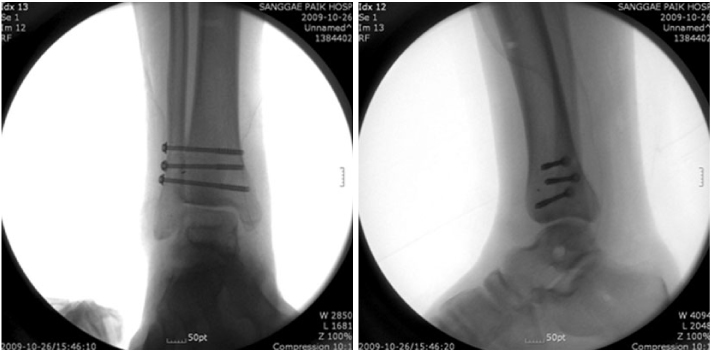

Fig. 4

(A) For initial treatment, open reduction and external fixation of ankle joint was done and a syndesmotic screw was inserted at other clinic.

(B) Follow-up X-ray with the external fixator removed 2 months later.

Fig. 4 (A) For initial treatment, open reduction and external fixation of ankle joint was done and a syndesmotic screw was inserted at other clinic. (B) Follow-up X-ray with the external fixator removed 2 months later.